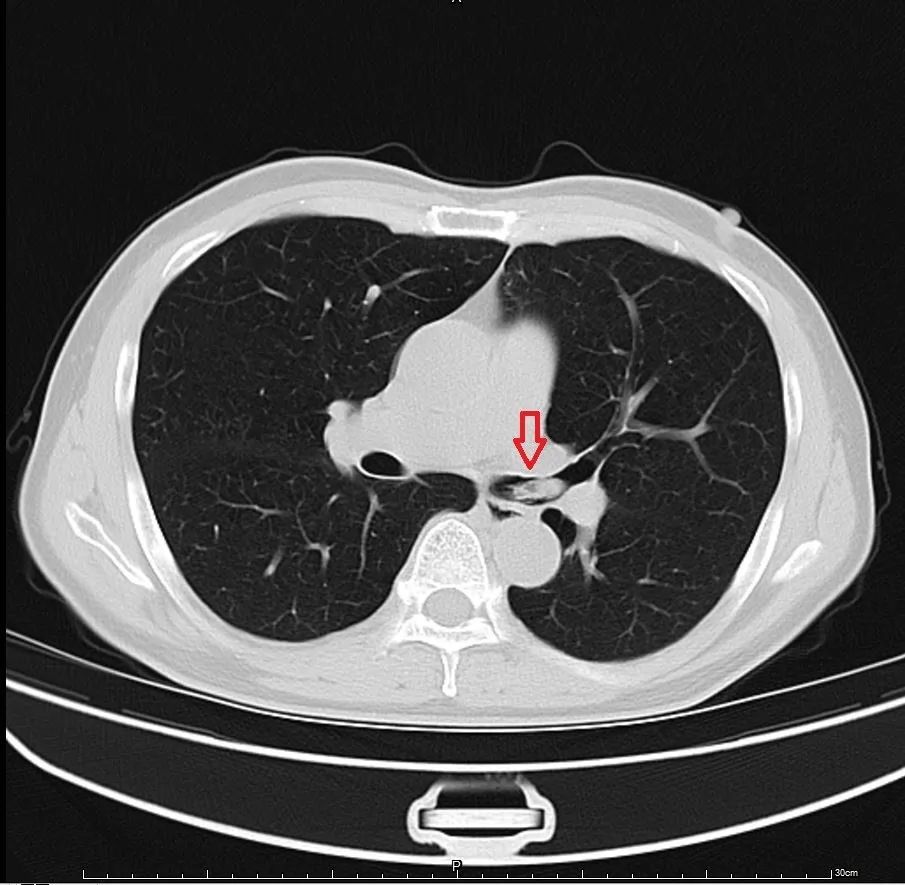

章医生:“你的胸部ct我看了下,是虾呛到气管里了,要马上在气管镜下取出来。”

(ct结果显示王先生的左肺有一只虾)